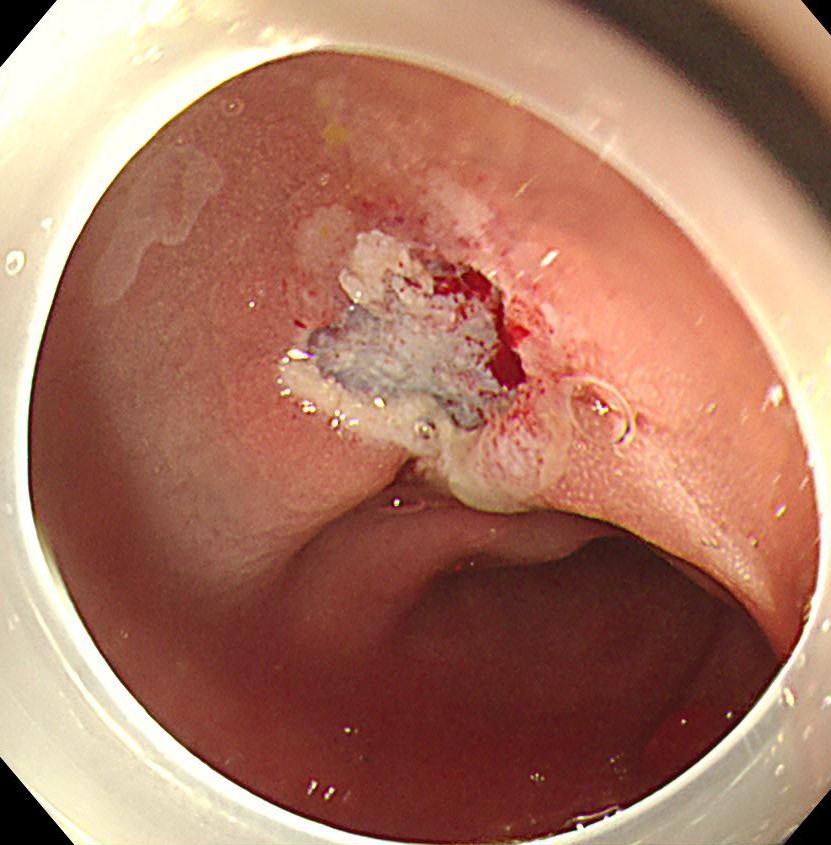

直腸S状結腸移行部に1型の腫瘍を認めます。

狭帯域光観察(NBI)では明らかにV型パターンであり、悪性を疑いますが、内視鏡治療可能と診断しました。

粘膜下に生理食塩水を局注し、ブルーのラインで切除します。

切除断端です。